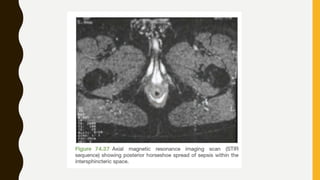

STIR Images

• STIR (Short TI Inversion Recovery) images, especially for spine and for musculoskeletal

imaging. STIR images have very low signal from fat but still have high signal from

fluids, i.e. they can be thought of as a ‘fat-suppressed T2w’ imaging technique.

• STIR is a type of IR sequence, like FLAIR, except that we choose to null fat-containing

tissues instead of CSF.